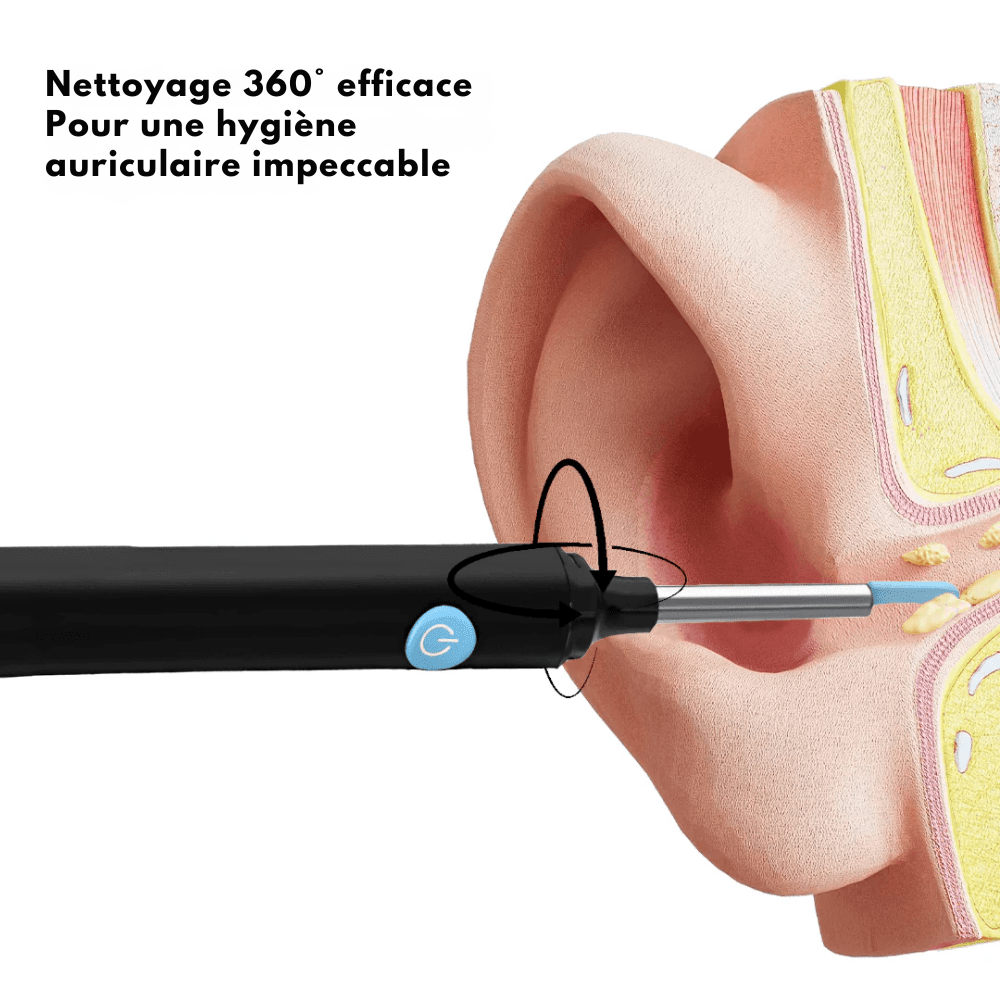

Oubliez les coton-tiges risqués, qui ne font que pousser le cérumen plus loin dans le conduit auditif, augmentant le risque de bouchons, d’inflammations ou de dommages auditifs permanents.

Une bonne hygiène auriculaire aide à prévenir les infections et les bouchons. Des oreilles propres favorisent une audition plus claire, et un entretien régulier contribue à ton bien-être général.

Grâce à sa caméra Full HD et ses 6 LED, obtenez une vision claire de l’intérieur de votre oreille directement sur votre smartphone.

Ses embouts souples assurent un nettoyage sécurisé et efficace, pour une audition optimale, comme elle devrait l’être.

Non, au contraire ! Grâce à la caméra HD, vous avez un contrôle total à tout moment. Les embouts souples sont spécialement conçus pour un nettoyage en douceur et sans douleur.